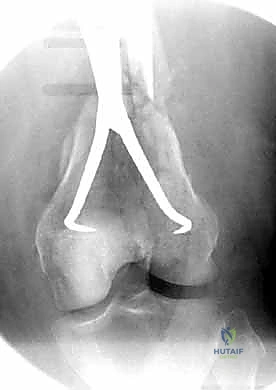

التشخيص الدقيق: حجر الأساس للعلاج الناجح

في عيادة الأستاذ الدكتور محمد هطيف في صنعاء، لا يتم ترك أي مجال للصدفة. يتم إجراء تقييم شامل يبدأ بـ:

- التقييم السريري المبدئي: فحص النبض والأعصاب للتأكد من عدم وجود إصابات وعائية أو عصبية مصاحبة.

- الأشعة السينية (X-Rays): أخذ صور من زوايا متعددة (أمامي خلفي، وجانبي) لتحديد موقع الكسر ونوعه.

- الأشعة المقطعية (CT Scan): وهي ضرورية جداً في كسور عظم الفخذ البعيدة، خاصة إذا كان الكسر يمتد إلى داخل مفصل الركبة (Intra-articular fractures). تساعد الأشعة المقطعية الدكتور هطيف على بناء نموذج ثلاثي الأبعاد للكسر، مما يسهل التخطيط الجراحي وتحديد أماكن وضع المسامير بدقة.